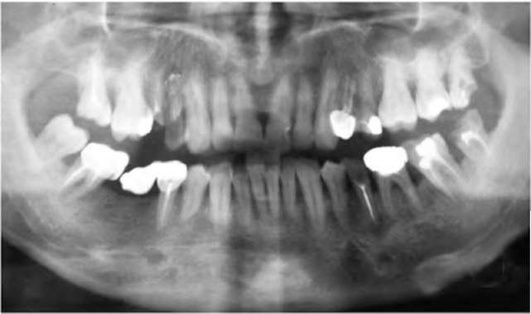

КЛИНИЧЕСКАЯ КАРТИНА

Клиническая характеристика периодонтита слагается из ряда симптомов и параклинических методов диагностики. Диагноз в целом ряде случаев может быть установлен лишь на основании всего комплекса данных, полученных при сборе анамнеза и применении различных исследований. Обследование пациента включает: жалобы, историю развития настоящего заболевания, статус здоровья, перенесенные и сопутствующие заболевания, клинические исследования (осмотр, пальпация, перкуссия); электроодонтодиагностику, рентгенологические исследования (внутриротовые и внеротовые рентгенограммы в различных проекциях, ортопантомограммы, фистулографию, радиовизиографию, компьютерную томографию и магнитно-резонансную томографию, специальные функциональные методы, лабораторные исследования (цитологические, патоморфологические, клинический анализ крови и иммунограмма, биохимические исследования, анализ мочи и др.).

Учитывая, что клиническая картина хронического периодонтита может отсутствовать или быть незначительно выраженной для дифференциальной диагностики обязательно проведение рентгенографии. На рентгенограмме определяют деформацию периодонтальной щели с нарушением четких контуров компактной пластинки кости альвеолы. Многие случаи хронического апикального периодонтита связаны с некачественным эндодонтическим лечением (рис. 13-7).

Диагностика основана на клинической картине и рентгенологических данных. На рентгенограмме при хроническом периодонтите обнаруживают типичные изменения - очаг разрежения костной ткани в области верхушки корня. Линия периодонта в этом отделе не видна из-за инфильтрирующего роста грануляционной ткани, приводящего к рассасыванию стенок лунки, а также цемента и дентина корня. Поверхности их становятся неровными. Эту неровность выявляют более отчётливо со стороны костной ткани, в которую из периодонта идут небольшие выросты. Компактную пластинку стенки альвеолы обнаруживают лишь в боковых отделах. У пациентов с периодонтитом и вовлечением в воспалительный процесс тканей пародонта происходит резорбция кости как по горизонтали, так и по вертикали.

Дифференциальная диагностика. Апикальную гранулёму следует дифференцировать от околокорневой кисты, особенно при выбухании кортикальной пластинки кости; хронического остеомиелита челюстей, брахиогенных свищей лица и шеи, актиномикоза, туберкулёза. Околокорневые гранулёмы чаще локализованы на верхней челюсти (63%), чем на нижней (37%). Наибольшее количество гранулём (54%) выявляют в области больших, а затем малых коренных зубов (38%).

При хроническом периодонтите с поднадкостничной гранулемой и околокорневой кисте имеется выбухание кости. Однако при кисте наблюдают смещение зубов, иногда отсутствует кость в области выбухания. На рентгенограмме при кисте присутствует очаг резорбции кости значительных размеров с чёткими ровными контурами; при периодонтите обнаруживают участок резорбции кости в среднем диаметром до 0,5-0,7 см.